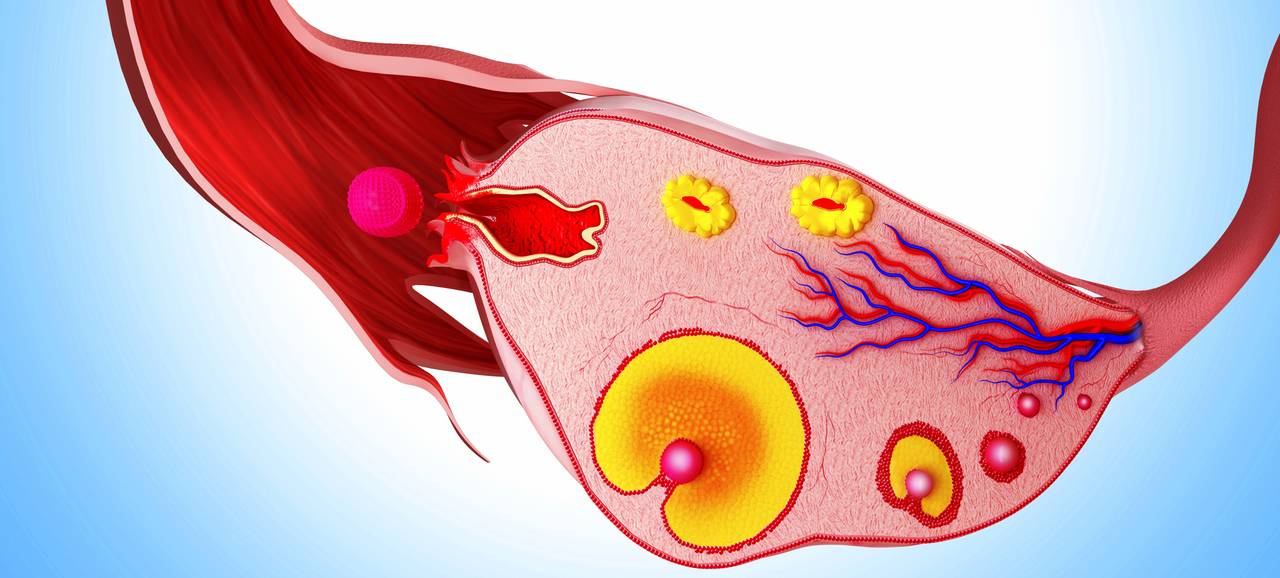

Созревание фолликула в яичнике: этапы и процессы

Раздел: Другие животные